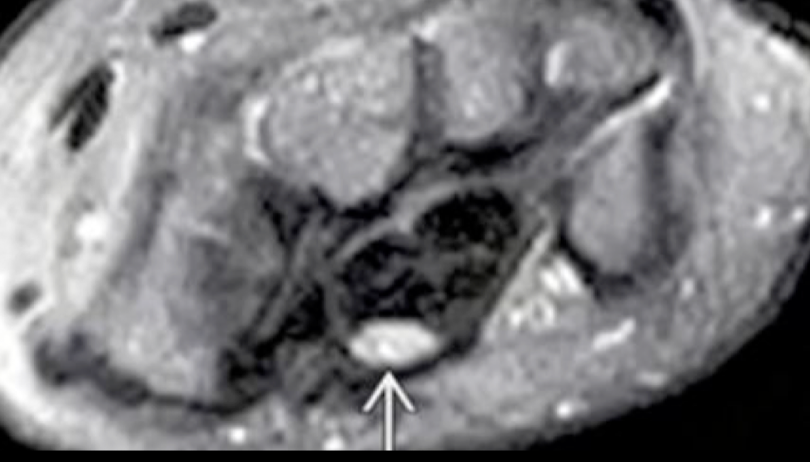

RM

Excelente

Hiperseñal T2 del tendón

edema subcutáneo peritendinoso

captación del contraste